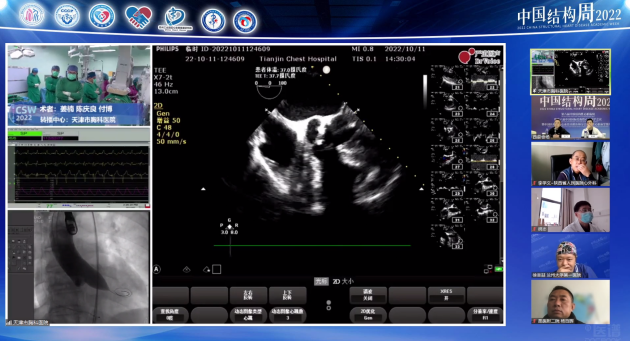

兰州大学第一医院白明教授团队带来一例中重度主动脉瓣狭窄(重度AS)伴钙化,依据患者病情手术策略如下:

Type0型二叶瓣,左右冠脉同窦,瓣叶略增厚,中重度钙化,钙化团块分布于无冠窦底及双侧瓣叶交界处,LVOT偏直筒型,预估瓣膜植入锚定难度适中,受交界处钙化影响,存在瓣周漏可能;

左、右冠高度可,切线位测量,无冗长瓣叶,结合瓦氏窦、STJ内径综合预估,冠脉阻塞风险适中;

左室内径偏小,术中密切关注血流动力学变化,适当补液;

横位心,升主无明显扩张,弓部宽度角度可,预估输送器可顺利过弓备snare在必要时辅助跨瓣,选择TaurusElite输送系统过弓跨瓣性能较佳;

股-髂动脉走行可,内径可,几乎无钙化分布,腹主动脉局部少许钲化分布,以右侧股动脉作为主入路;

跨瓣、球扩、瓣膜植入共同采用双窦展开角度RAO 22 CAU 20左右;

备用角度:左冠切线位LAO O CRA 30。

术中针对球扩瓣size选择、如何预防瓣周瘘、横位心造成的高低瓣等问题展开细致研讨。术中选用18mm球囊预扩张,考虑到患者二叶瓣,依据瓣环而不是瓣上结构选择瓣膜大小,瓣膜选择瓣叶展开较好的球扩瓣downsize,其不容易下滑稳定性较好。术后造影显示高低瓣,少量反流,血流动力学很好,主动脉瓣峰值流速1.5m/s。术后分析反流原因可能是左冠瓣裙边位置在流出道,造影剂通过网眼流出,但若选择大一些瓣膜,瓣膜移位可能性相应会增加,故术后随时关注瓣膜展开情况,若瓣叶对合没问题少量反流可以接受。